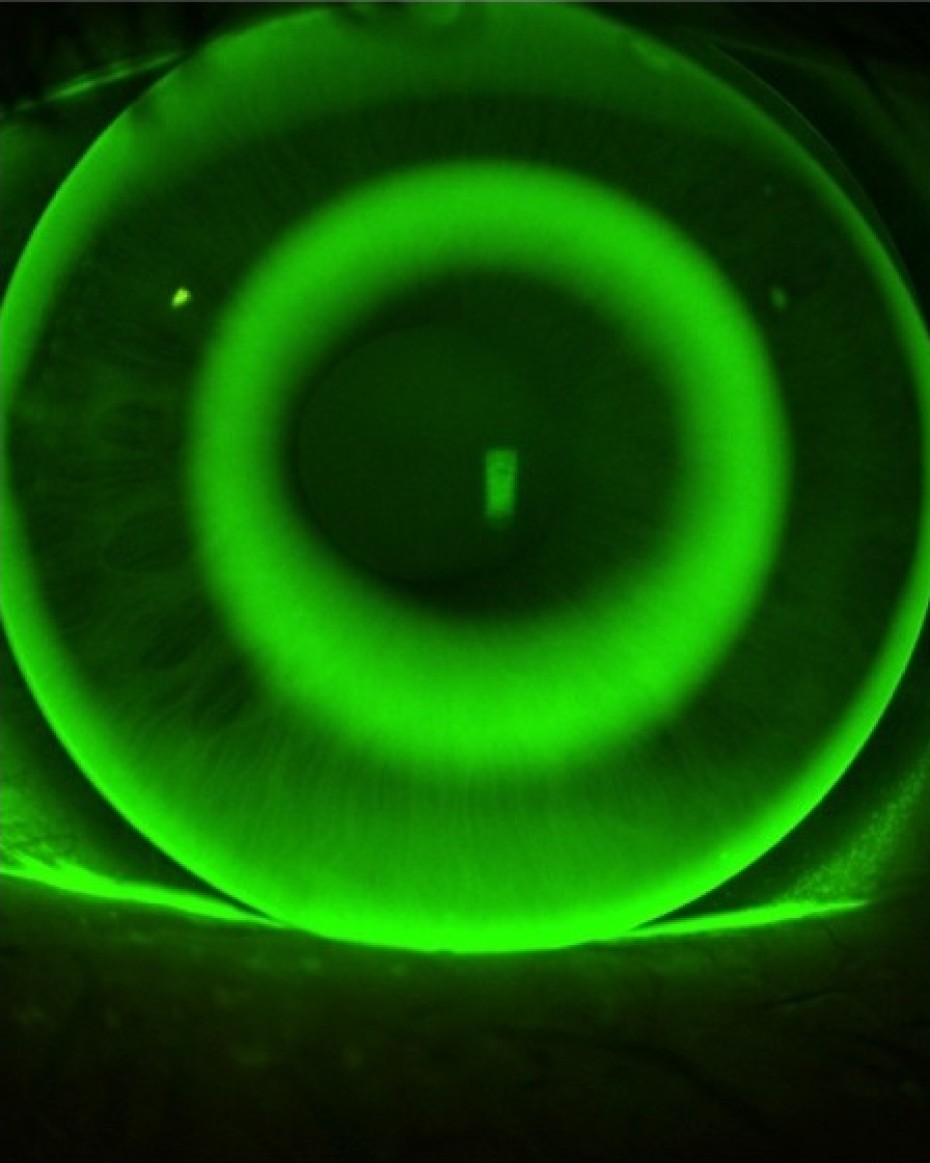

Messung an Spaltlampe

Alle 6 Monate kostenlose Nachkontrolle

Sehstärkenüberprüfung und Sitzkontrolle der Kontaktlinse sowie eine Inspektion der Augen garantieren langfristige Zufriedenheit